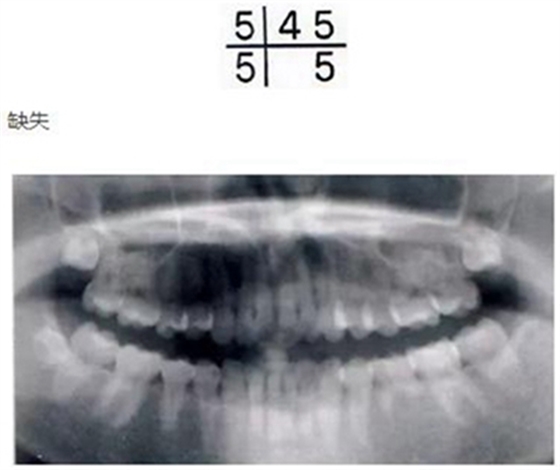

乳牙的晚期殘存(恒牙的先天性缺失)

[原因不明的多顆恒牙先天性缺失病例(17歲)]右下E殘存,